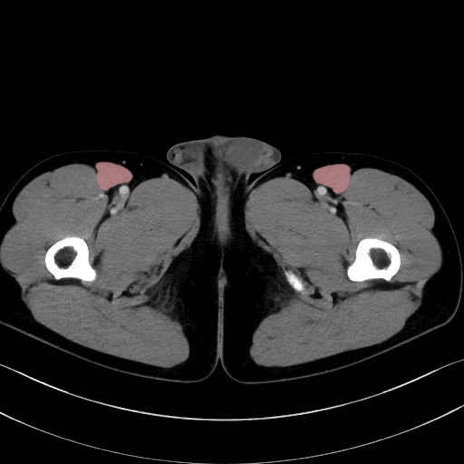

縫工筋 (Sartorius)

大腿直筋 (Rectus femoris)

外側広筋 (Vastus lateralis)